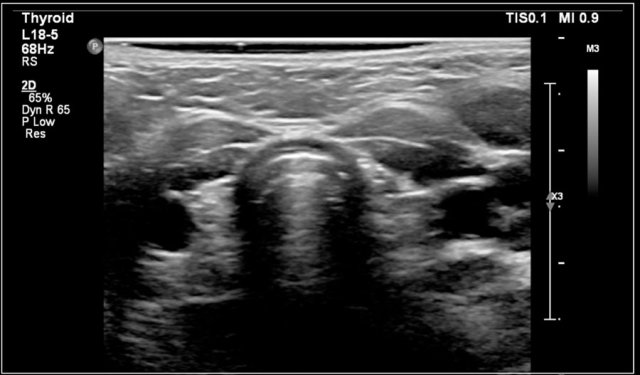

The most common forms of thyroiditis are Hashimoto's thyroiditis and Graves disease.

Both Hashimoto's thyreoiditis and Graves disease can present as an enlarged and hyperemic thyroid.

On ultrasound the gland is diffusely enlarged and inhomogeneous.

On color doppler the blood flow is often normal but can be increased like in Graves' disease.

In a later stage the gland shrinks.

In Graves disease the thyroid gland is also enlarged and shows an increased perfusion.

On color Doppler it has been described as an inferno in red and blue.